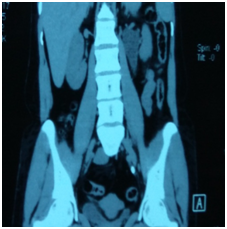

All patients who reported within 1-2 days of ureteric colic were examined, and subjected to Haemogram, KFT, Urine examination, Ultrasound and NCCT Scan (Figure 1&2) to document ureteric calculi at the time of colic with respect to location, side and size of the stone. Age and sex of the patient was noted down and SOADS regime was started for a period of 4 weeks maximum after which this MET was stopped. The routine follow up examination were performed, using the same tools to evaluate the success of the treatment after every week till 4 weeks of study period. Patients were instructed to discontinue the study medication after spontaneous stone expulsion and date of expulsion is to be recorded. For patients without stone in urinary tract on final USG/NCCT but unnoticed stone expulsion, the date of last positive stone status is to be recorded (Figure 3). For the children the dosage of the SOADS regime was half the dosage. Two - three litres of fluid which consists of Lemon juices, Oranges juices and clear water or Tea. This regime was continued for 2 weeks after which again assessment was made and if the stone did not pass then it was continued for another 2 weeks. Treatment was considered successful when stone was expelled within 4 weeks. After 4 weeks, patients who did not pass the stone were advised to undergo minimally invasive surgery depending upon the stone size and location.

Figure 3 NCCT Scan of abdomen & Pelvis showing left lower ureteric calculi.